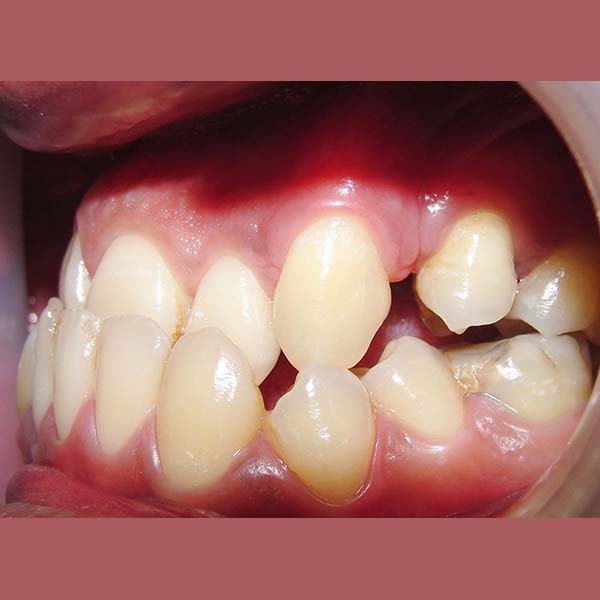

AFTER

After examining the case, I have conveyed the good news to our friend, that despite the difficulty of his case, we were able to reach a satisfying result through orthodontic treatment. As expected, tooth extraction was nessecary, to open space for the rest of his teeth to arrange and treat the anterior crossbite. At the end of the treatment, most of our friend’s dental problems were treated, and he could smile happily and with confidence.